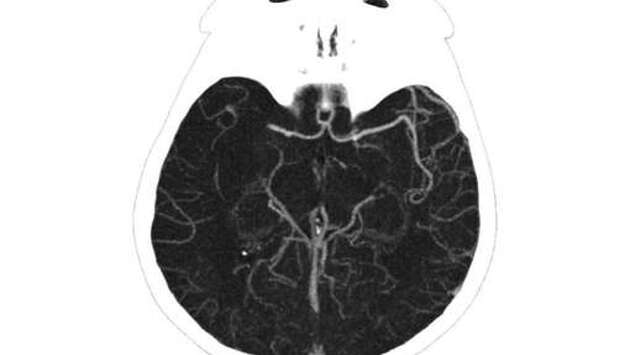

Московские хирурги спасли молодую женщину от инсульта, удалив огромный тромб из мозговой артерии. Об этом сообщает столичный Депздрав. 25-летняя женщина поступила в ГКБ им. М.П. Кончаловского с жалобами на головокружение, слабость и онемение конечностей. Медики диагностировали у нее ишемический инсульт. "Из артерии удалось извлечь червеобразный сгусток длиной 25 см. Изначально мы даже заподозрили, что в сосуде мозга женщины поселился паразит. Но исследования показали, что это все-таки тромб", — рассказал руководитель регионального сосудистого центра Владимир Кузнецов. После операции пациентка прошла углубленное обследование, которое показало, что у нее развилось опасное аутоиммунное заболевание — антифосфолипидный синдром, при котором возрастает риск образования тромбов в артериях и венах. Женщине подобрали лечение, которое в дальнейшем будет препятствовать образованию тромбов.